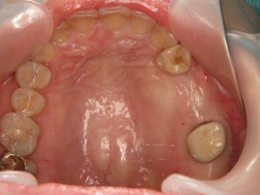

歯周病と根の治療を終わらせた後でインプラントを埋入しました。今では何でも噛めます。

奥歯は骨が少なく、骨をつくり、インプラント治療をしました。赤く囲ったところが出来た骨です。